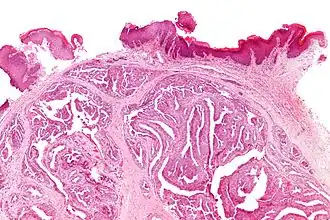

Micrografía de un hidroadenoma papilar en que se aprecian las estructuras características. | ||

El hidroadenoma papilar es una neoplasia benigna. Nódulo bien delimitado localizado sobre todo en los labios mayores de la vulva y pliegues interlabiales.[1] Puede confundirse con un carcinoma, por su tendencia a ulcerarse. Surge a partir de las glándulas sudoríparas apocrinas de la vulva, que son modificadas. Microscopicamente tiene un aspecto idéntico a los papilomas intraductales de la mama. Está formado por proyecciones papilares compuestas de dos capas de células, una capa de células secretoras superiores y otra inferior de células mioepiteliales.